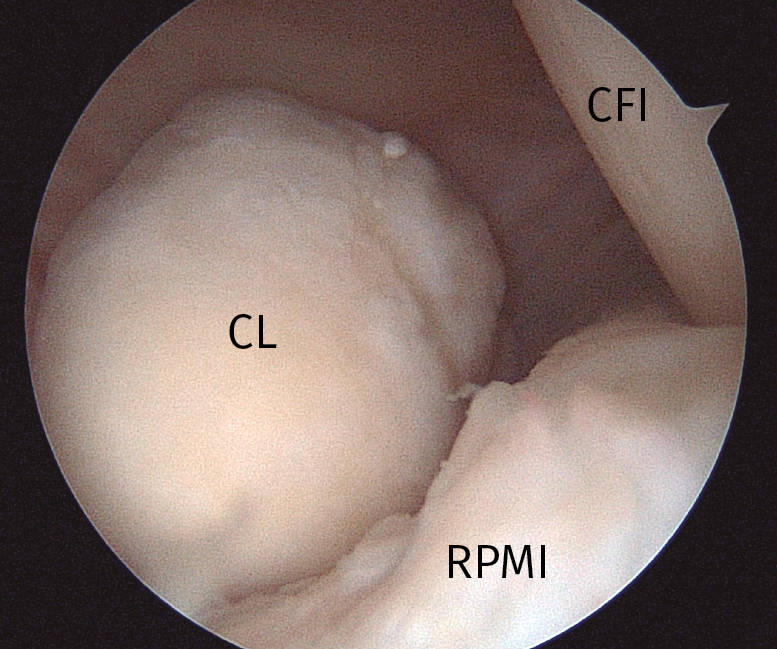

Las indicaciones en las que puede ser necesario emplear portales posteriores son muchas. En ocasiones, puede evitar la realización de un abordaje posterior abierto que, además de la mayor agresión quirúrgica, puede ofrecer una visión más limitada que la artroscopia. Así, el abordaje artroscópico de los compartimentos posteriores ha sido utilizado para la sinovectomía(14), meniscectomía(15), reparación de raíces posteriores de los meniscos(16), reparaciones de la rampa posterior del menisco interno(17), reconstrucción del ligamento cruzado posterior (LCP)(18), fijación de una fractura-avulsión tibial del LCP,(19), capsulotomía posterior en casos de artrofibrosis(20), extracción de cuerpos libres intraarticulares(21), sinovitis villonodular(22), reconstrucción del LCA(23), condromatosis sinovial(24) y resección de quistes y gangliones posteriores(25). Además de estas indicaciones publicadas, recomendamos la realización sistemática de portales posteriores en el tratamiento artroscópico de las artritis sépticas de rodilla para un adecuado desbridamiento y lavado de los compartimentos posteriores (Figura 1).

Figura 1. Imagen del compartimento posteromedial desde una visión transescotadura desde el portal anterolateral, rodilla derecha. Se evidencia la presencia de un cuerpo libre “oculto”. CFI: cóndilo femoral interno; CL: cuerpo libre; RPMI: rampa posterior de menisco interno.